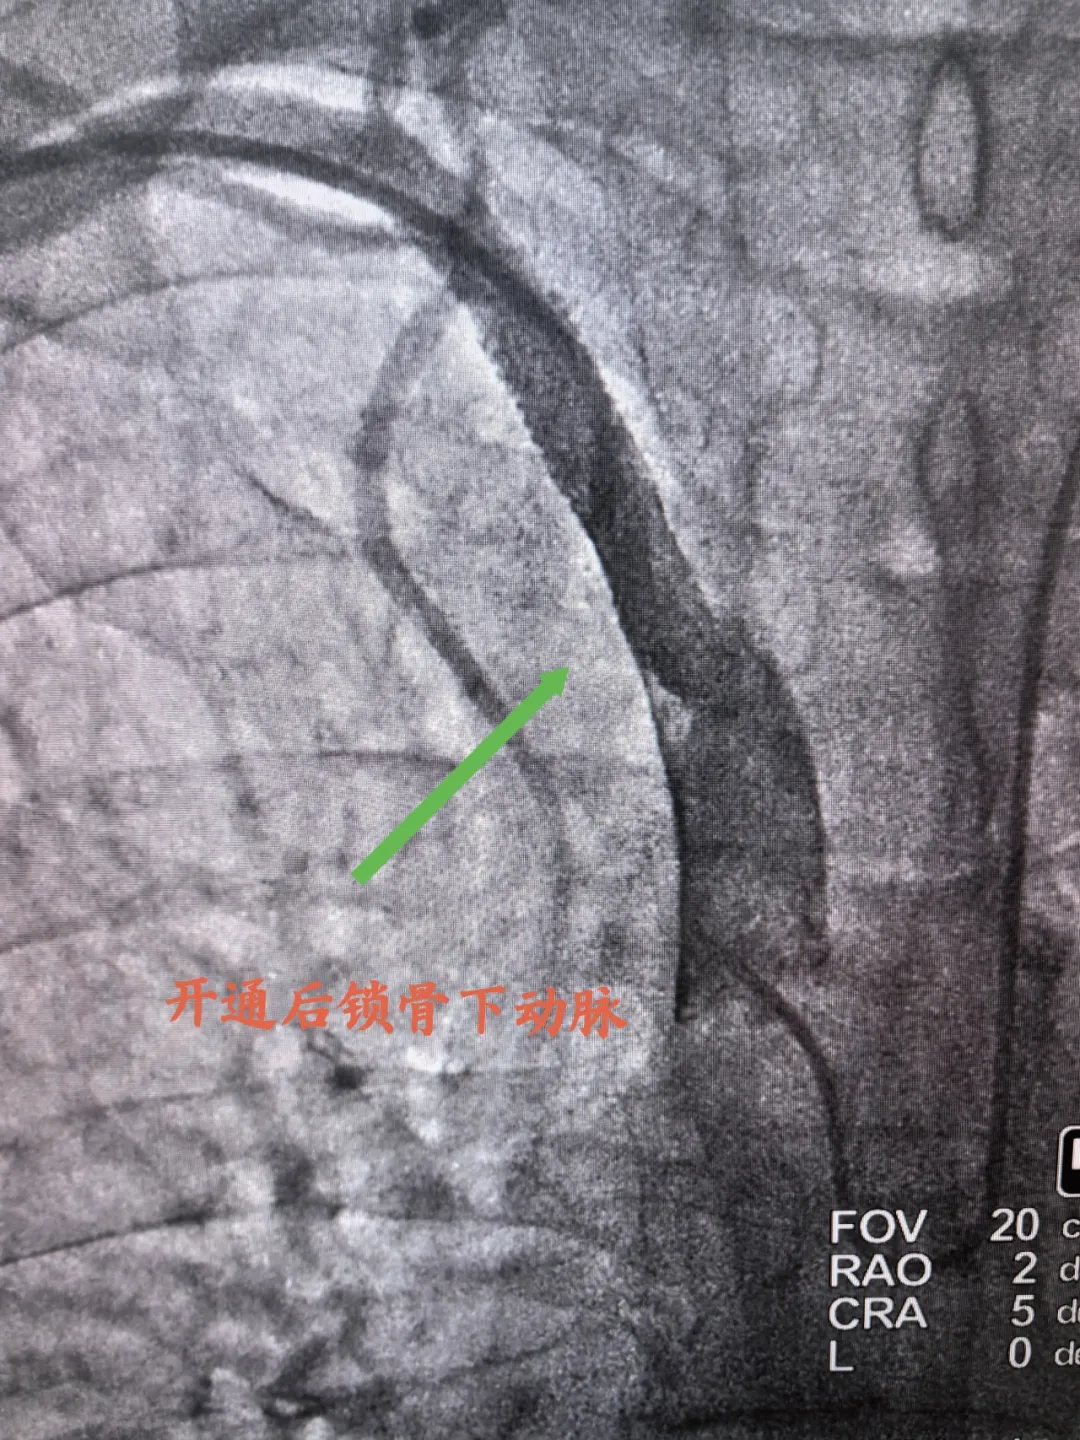

開通后鎖骨下動脈

造影結(jié)束后,介入診療組經(jīng)過討論后,考慮患者不能長時間臥床,不適合穿刺股動脈,故選擇雙側(cè)橈動脈,“一站式”開通閉塞鎖骨下動脈及冠脈介入治療,術(shù)中成功為患者開通閉塞右鎖骨下動脈,并成功完成冠脈兩處病變介入治療,整個手術(shù)一氣呵成,過程不到3小時。術(shù)后患者測量右上肢血壓達120/70mmHg,他驚嘆道:“我胸悶、氣短好多了,右手能摸到脈了”。